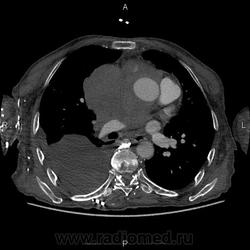

ID:50390

Ничего себе... Опухоль средостения с прорастанием ВПВ, ПГС, сердца, и мтс по плевре? Коллатерали показательные. Или первично образование сердца... саркома какая-нибудь?

да уж ! красиво, только много непонятного. Первично похоже поражено сердце , а потом распостранение по легочным сосудам и полой вене. В печени тоже какой то очаг.. Коллатерали ..как пуховый платок

Если интересно, то разбирать всё нужно по порядку. Контрастный препарат попал аж в общие подвздошные вены больше, чем в аорту.

Итак, начали исследование, выставили уровнень смартпрепа (болюс-трекинга или как угодно), после введения контрастного препарата, его не огтмечалось в аорте и лишь через 40 секунд начал появляться. Так получилось вследствие полного тромбоза верхней полой вены. Соответственно, сброса внеё из вен верхней конечности не происходило. По такой венозной сети (первый слайд) контрастный препарат попадает в НПВ и лишь после этого в камеры сердца и далее. Итак, картина достаточнот редкая, но типичная для саркомы. Локализация - праве предсердие. На гистологии - низкодифференцированная саркома.